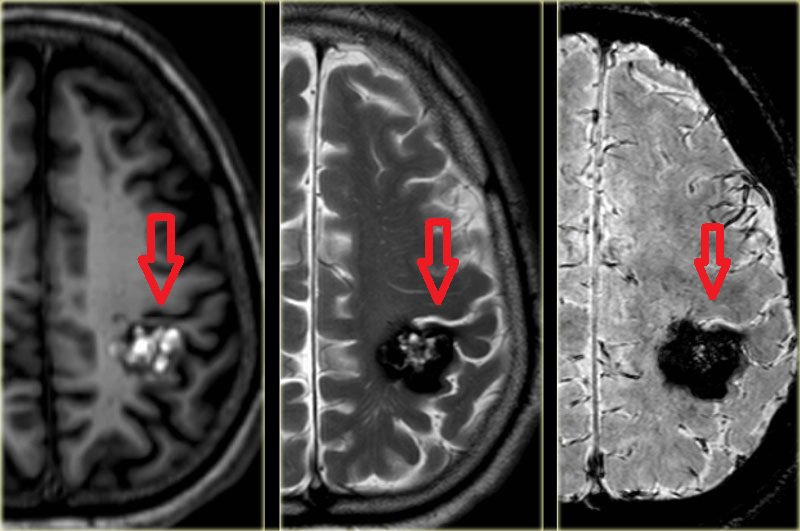

Chụp cộng hưởng từ (chụp MRI) là kỹ thuật Chẩn đoán hình ảnh kiểm tra não bộ, có thể cho thấy vị trí não bộ bị tổn thương hoặc phát triển không bình thường. Chụp MRI bại não sử dụng sóng vô tuyến và từ trường để tạo ra hình ảnh 3D hoặc hình ảnh cắt lớp chi tiết của bộ não. Từ đó, bác sĩ có thể xác định được những tổn thương hoặc bất thường nếu có trong não bộ. Phương pháp này không gây đau nhưng có thể gây ồn, thường kéo dài trong khoảng 1 giờ. Trẻ sẽ được sử dụng một liều thuốc an thần nhẹ trước khi chụp MRI.

Tất cả trẻ bị nghi ngờ hoặc giả định bị tổn thương não nên được chụp cộng hưởng từ. MRI là kỹ thuật hình ảnh học Thần kinh tiêu chuẩn vàng để xác định bệnh bại não - tổn thương chất trắng não ở trẻ bao gồm nhuyễn não chất trắng quanh não thất, các tổn thương chất xám ở sâu, các dị dạng, các cổ nhồi máu, các tổn thương vỏ não và dưới vỏ. Tuy vậy, lưu ý rằng có khoảng 12 - 14% trẻ bại não có kết quả chụp MRI bình thường nên chẩn đoán xác định bại não không nên phụ thuộc hoàn toàn vào MRI mà cần phối hợp với các phương pháp chẩn đoán khác như siêu âm não, chụp cắt lớp vi tính (CT scan) não, điện não đồ, Xét nghiệm máu,...

Phương pháp chụp cộng hưởng từ có thể cung cấp cho bác sĩ một số thông tin để dự báo chức năng. Cụ thể, các tổn thương chất trắng quanh não thất khi phát hiện bằng chụp cộng hưởng từ có thể gợi ý về tình trạng khiếm khuyết vận động nhẹ hơn (trẻ có thể đi được). còn các tổn thương vỏ não, dưới vỏ và hạch nền khi phát hiện bằng chụp MRI sẽ gây ra những khiếm khuyết về vận động nặng hơn (trẻ không thể đi được).